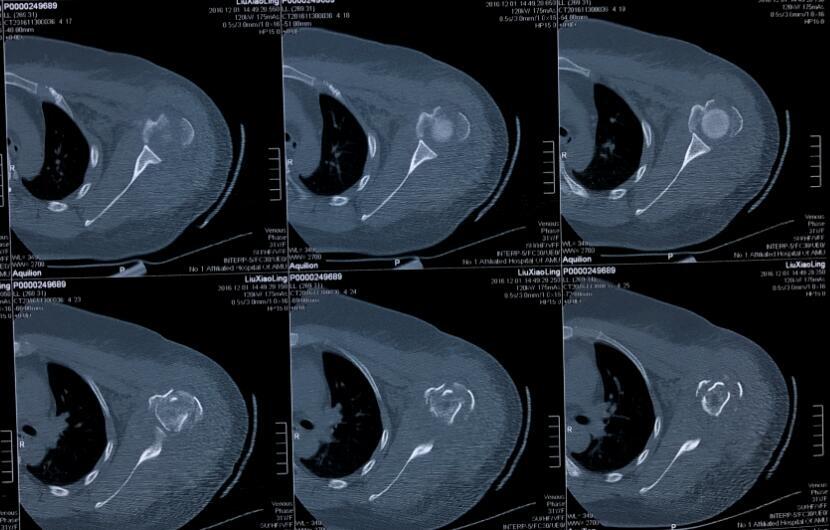

近日,我院关节与显微修复外科利用锁定钢板固定联合同种异体腓骨髓内移植成功治疗一例复杂肱骨近端骨折患者。该患者为31岁,女性,左肩车祸伤。术前射片诊断为左侧肱骨近端骨折(Neer’s四部分骨折)。我科胡孔足主任术前结合患者病史,体检及辅助检查,制定了详实的手术方案,手术顺利,术后患者恢复满意。据悉,利用锁定钢板固定联合同种异体腓骨髓内移植治疗肱骨近端骨折为安徽省首例,标志着我院在复杂肱骨近端骨折修复重建治疗上迈出坚实一步。

四部分肱骨近端骨折骨折复位后遗留严重骨缺损,术后易发生螺钉松动,肱骨头再移位、内翻移位等并发症,通常采用关节置换术治疗。由于人工关节有一定使用寿命,对于年轻患者,受到一定限制。联合引用同种异体腓骨髓内固定,能够使肱骨头获得有效支撑,内侧柱得到加强,并增加肱骨近端骨量,使锁定钢板固定更加稳定,允许患者早期功能锻炼。该技术在国外有4-5年使用经验,国内少数医院已经开展,安徽省属于首例。